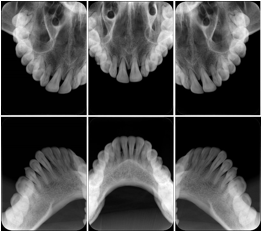

3. A dental provider wishes to capture a series of DICOM IO images for the patient’s dentition. The tooth morphology, teeth are divided into molars, premolars, canines and incisors, and a number of images for each jaw. The anatomic information was captured utilizing the triplet of schema. This standard code sequence is based on ISO 3950-2010, Dentistry - Designation system for teeth and areas of the oral cavity.

Every IO image should have anatomic information either through the primary or modifier sequence.

In most standard cases, images are oriented in structured layouts. These structured displays are useful to be shared between providers for reference purposes.

Table OO.1.1-1 shows structured display standard templates, where Viewset ID is based on the Japanese Society for Oral and Maxillofacial Radiology (JSOMR) classification provided by JIRA (Japan Medical Imaging and Radiological Systems Industries Association, www.jira-net.or.jp). Expected or typical teeth to be imaged location, region and designation codes are based on ISO 3950-2010, Dentistry - Designation system for teeth and areas of the oral cavity. For all the hanging protocols listed in OO.1.1-1, the value to use for Hanging Protocol Creator (0072,0008) is "JSOMR" and the value to use for Hanging Protocol Name (0072,0002) does not include "JSOMR" (e.g., "DL-S001A", not "JSOMR DL-S001A").